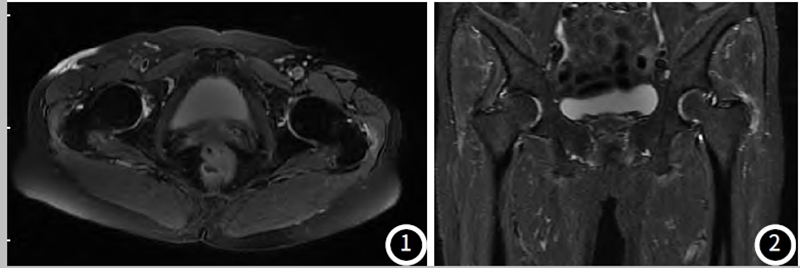

MRI被认为是诊断GTPS的主要方法,它能评估臀肌的形态和大小、转子区的滑囊炎、臀肌肌腱炎、臀肌撕裂、周围软组织水肿及股骨大转子骨髓水肿或囊变等表现。